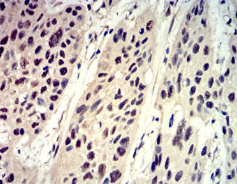

Phospho-4E-BP1 (Ser65)单克隆抗体[1E2E7]

Phospho-4E-BP1 (Ser65) Mouse Monoclonal antibody[1E2E7]

IHC    1/200 - 1/1000